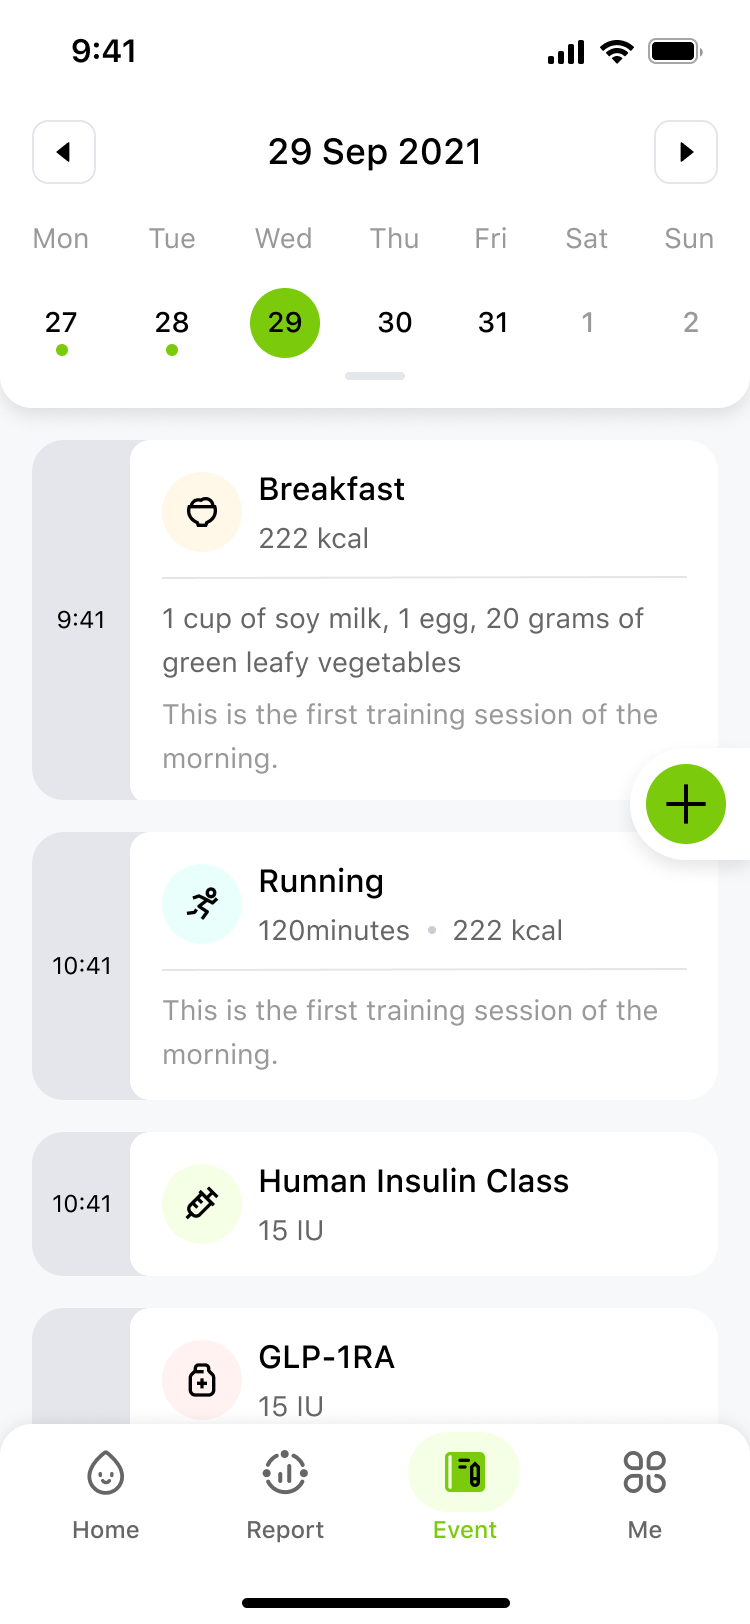

Turn your continuous glucose data into actionable insights. Unlock how your diet, exercise, and sleep personally affect you. Easily monitor your levels and generate professional reports anytime, anywhere. This is health management, simplified—putting you in control of your future.

Digital Solutions